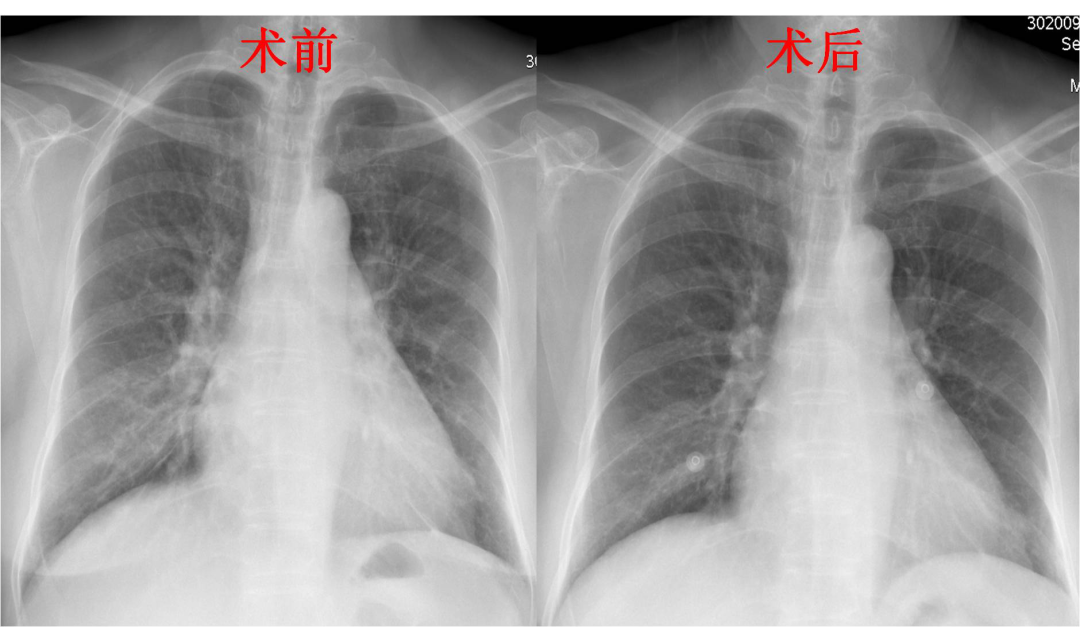

图解:术前患者双肺淤血重,术后双肺淤血明显缓解。